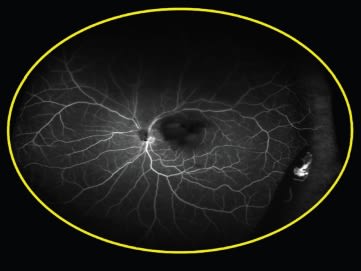

The second case Dr. Freund presented also used ultra widefield FA. This patient, a 55-year-old white woman, presented with what appeared to be posterior vitreous detachment–related symptoms, including the sudden onset of floaters related to a vitreous hemorrhage (Figure 1). The ultra widefield FA revealed instead that the problem arose from neovascularization related to peripheral nonperfusion; the fellow eye showed the same problem (Figures 2 and 3).

Figure 2. Ultra-widefield FA revealed neovascularization related to peripheral nonperfusion.